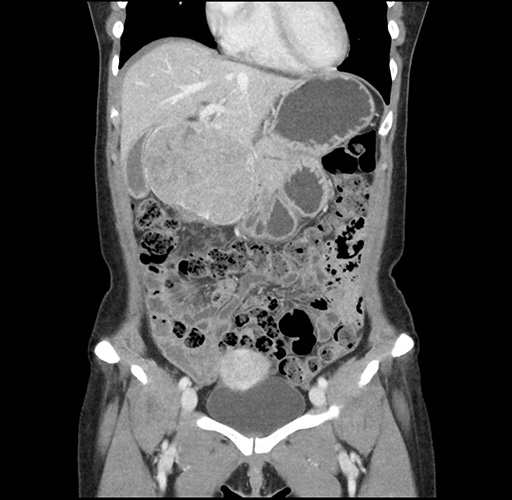

Imaging Analysis

Look through the patient's CT scan to identify any areas of concern for the necessary procedure.

Based on your CT findings, which issue(s) would give reason for "planned slowing down moment(s)" in this case?

Considering a standard left lateral sectionectomy procedure, what step(s) of the operation would you do differently in this case ?